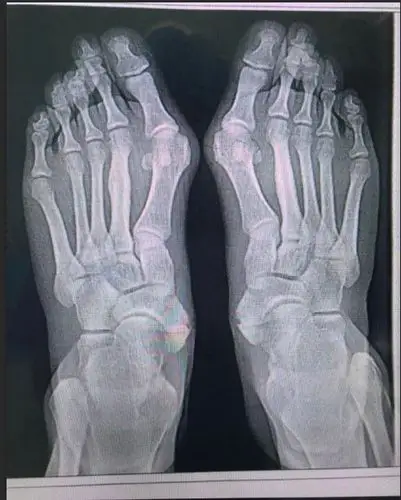

x光片更直观了解大脚骨 如果单纯去掉凸起能否有效矫正拇外翻呢?